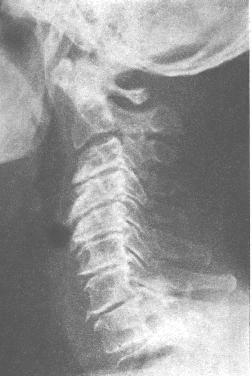

答:在X光片上,我们可以发现,正常人的颈椎“队列”本应是弯的,象香蕉果(见下图左)。

而颈椎病人的“队列”,变直了,象铅笔(见下图右)。

尤其青壮年的颈椎病人,其X线表现,仅仅是生理曲度改变(变直或反曲)。

患病久的颈椎病人,其X线表现比较多,但其“始发”病变是——颈椎“队列变直”。

他们都有一个共同的病变特点,那就是———颈椎 “队列”,变直了,甚至反弯了。

大多数颈椎病人的“骨质”并不增生,在拍摄的X线片上只发现颈椎“生理曲度”变直或消失(如下图)。

所以说,有“骨质增生”的人不一定有颈椎病,有颈椎病的人不一定就有“骨质增生”,这是两码事,不应该混为一谈。